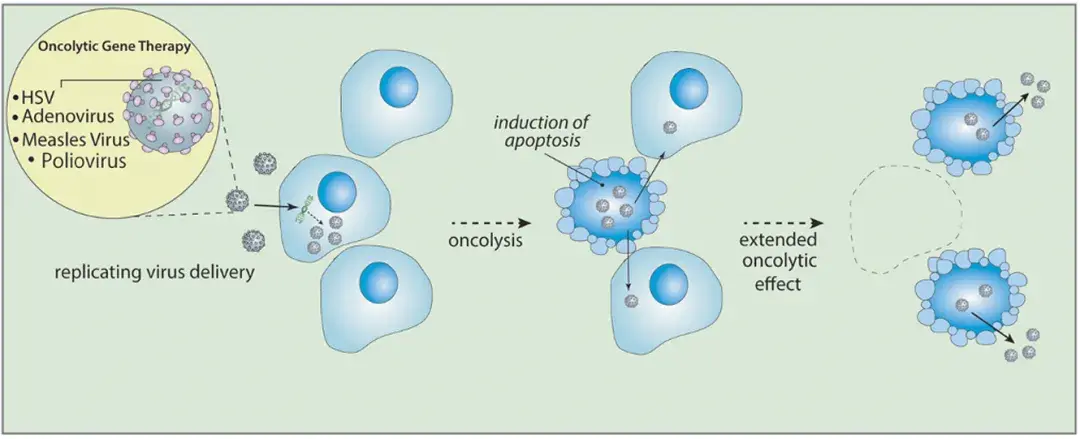

阅读前文: 胶质母细胞瘤的基因治疗:这种特别的基因治疗有哪些优缺点? 病毒载体发展的一个主要焦点是创建基因工程腺病毒和逆转录病毒。溶瘤病毒是一类具有复制能力的肿瘤杀伤型病毒...